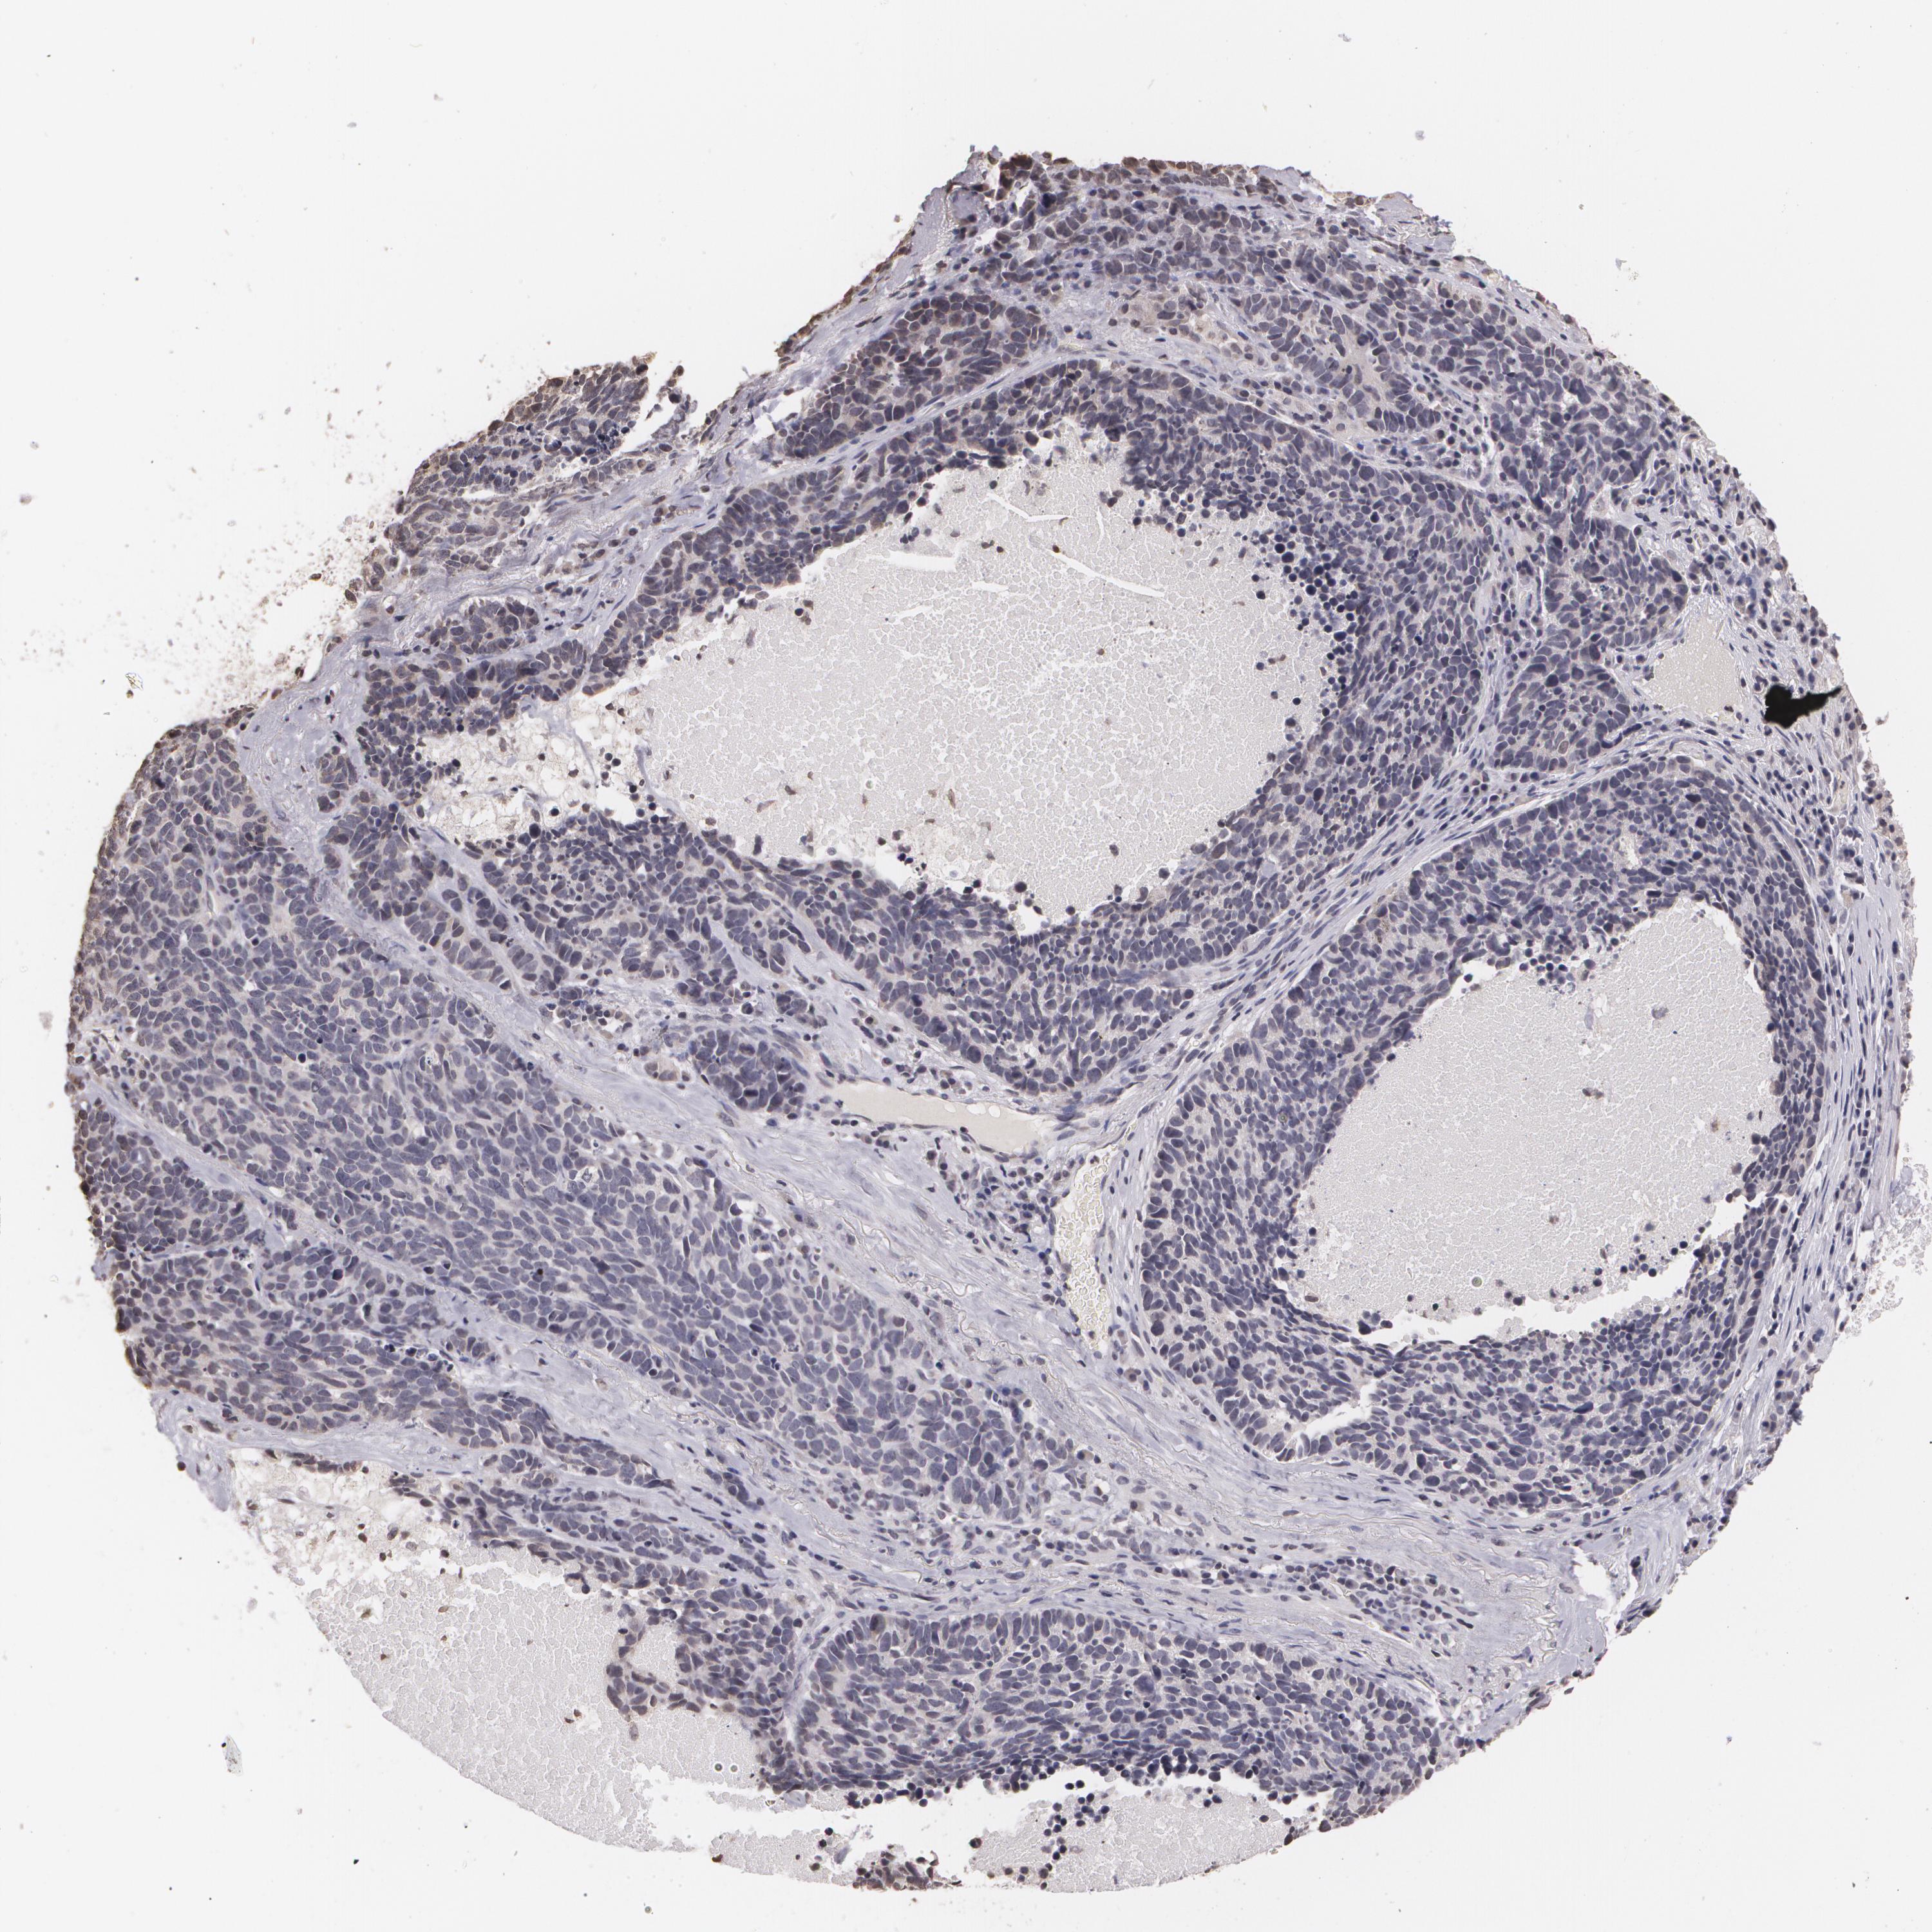

THRB is not prognostic in Lung Adenocarcinoma (validation)

Best expression cut offi

When clicking on this number, the vertical dashed line indicating cut-off, the interactive survival plot, and the Kaplan-Meier curve will be adjusted to show results based on the best expression cut-off.

: 2.98

P scorei

N/A

5-year survival highi

For melanoma and glioma, 3-year survival is shown.

5-year survival lowi

Average pTPM 4.0

Number of samples 105